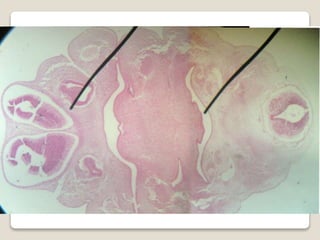

Surcos faríngeos

 Surco formado entre arco y arco.

 Entre 4ta y 5ta semana,

hay cuatro surcos a cada

lado. A inicios de la 6ta

semana, solo queda el 1er

surco que formará al

conducto auditivo externo.

Los demás obliteran después

de formarse el seno cervical.